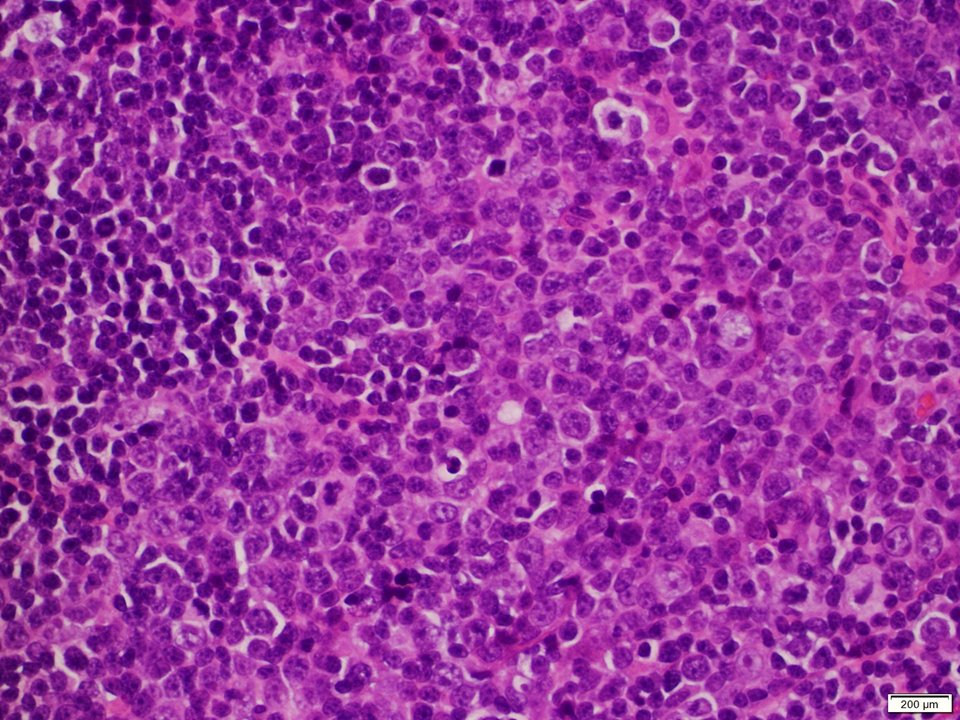

(1/3) Mutlifocal DLBCL arising in a background of low grade follicular lymphoma, with a peculiar architecture #hemepath #LJMFridayUnknowns #VirtualHemepathMDA #lymsm #endcancer

(3/3) High power view of the large cell transformation component (with numerous centroblasts and immunoblasts), and adjacent FL component #hemepath #LJMFridayUnknowns #VirtualHemepathMDA #lymsm #endcancer